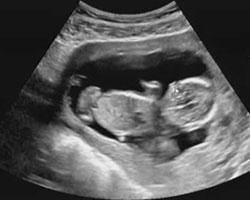

O desenvolvimento do feto no primeiro trimestre de gravidez foi algo extraordinariamente rápido. Talvez te tenham feito uma ecografia há algumas semanas e pudeste ver o bebé que cresce na tua barriga… Mas mudam tão rápido! Na 14ª semana já se assemelha ao que podes ver neste vídeo e nesta ecografia.

Ecografia 14 semanas